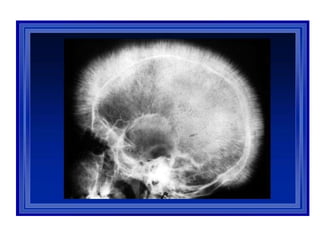

X ray skull:

“ hair on end”

appearance

or

“crew-cut”

• Small bones (hand ) – earliest bony change,

rectangular appearance,medullary portion of

bone is widened &bony cortex thinned out

with coarse trabecular pattern in medulla

• Skull – widened diploid spaces – interrupted

porosity gives hair on end appearance

• Delayed pneumatization of sinuses – maxilla

appears overgrown with prominent malar

eminences